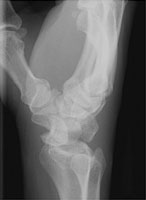

The lunate dislocation results from a backwards fall on an outstretched hand. Here, the capitate is aligned with the radius on the lateral view with volar displacement of the lunate. This is the most severe injury on the perilunate continuum with the greatest number of intercarpal ligaments disrupted.

- Click on the image for a larger versionALateral radiograph of the wrist. This shows volar displacement of the lunate.